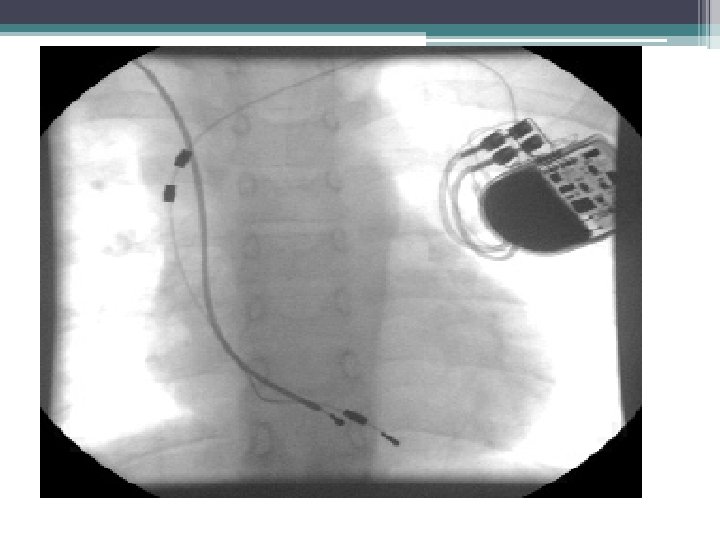

15 year old boy with postoperative AV block. VDD pacemaker. Needs biventricular pacing. What to do? ? ?